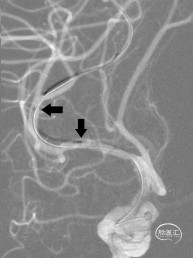

术前影像资料

诊疗经过